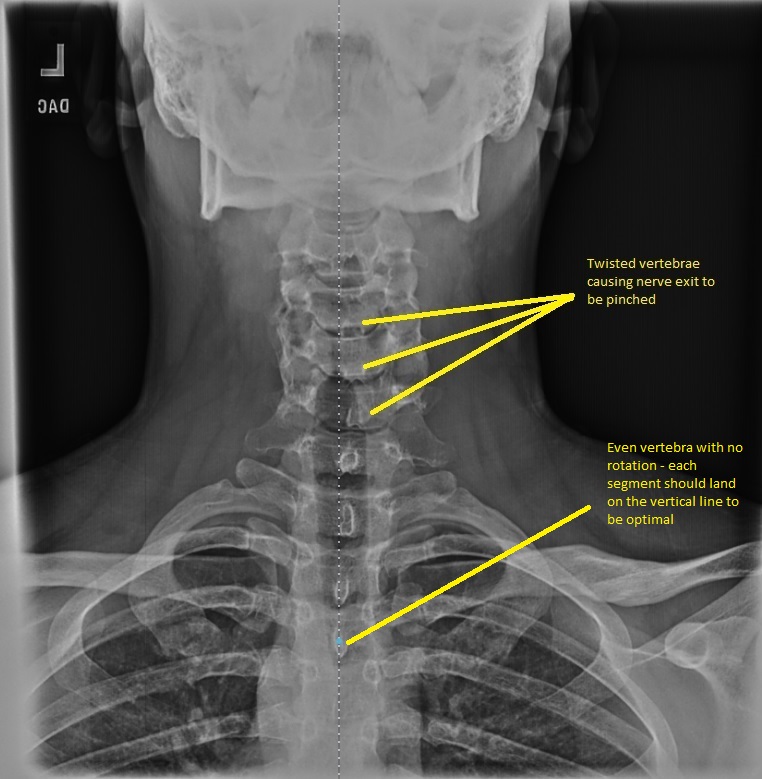

Dr. Asher uses state-of-the-art X-ray technology to asses each patient’s underlying skeletal structures. If necessary for your condition, we may suggest X-rays. These X-rays are essential for creating the most effective treatment plan and identifying any significant spinal conditions. Reviewing your X-rays up close can provide valuable insight, helping you gain a better understanding of your condition and available treatment options.